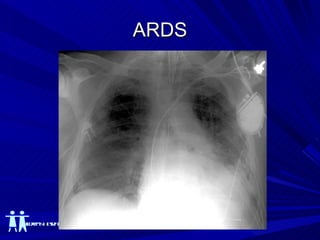

Rayos X - Torax ¨ Se piensa que los infiltrados radiográficos deben  ser bilaterales y deberían ser consistente con edema pulmonar, es importante saber que los infiltrados  pueden ser moderados ¨ Bernard G.R. et al. AJRCCM 1994 149-818

Rayos X - Torax 21 expertos revisaron 28 Rx: 43% de los Rx: completo acuerdo 32% de los Rx: desacuerdo significativo % de consistencia ALI / SDRA: 36  71% Rubenfelt et al Chest 118 – 566 2000